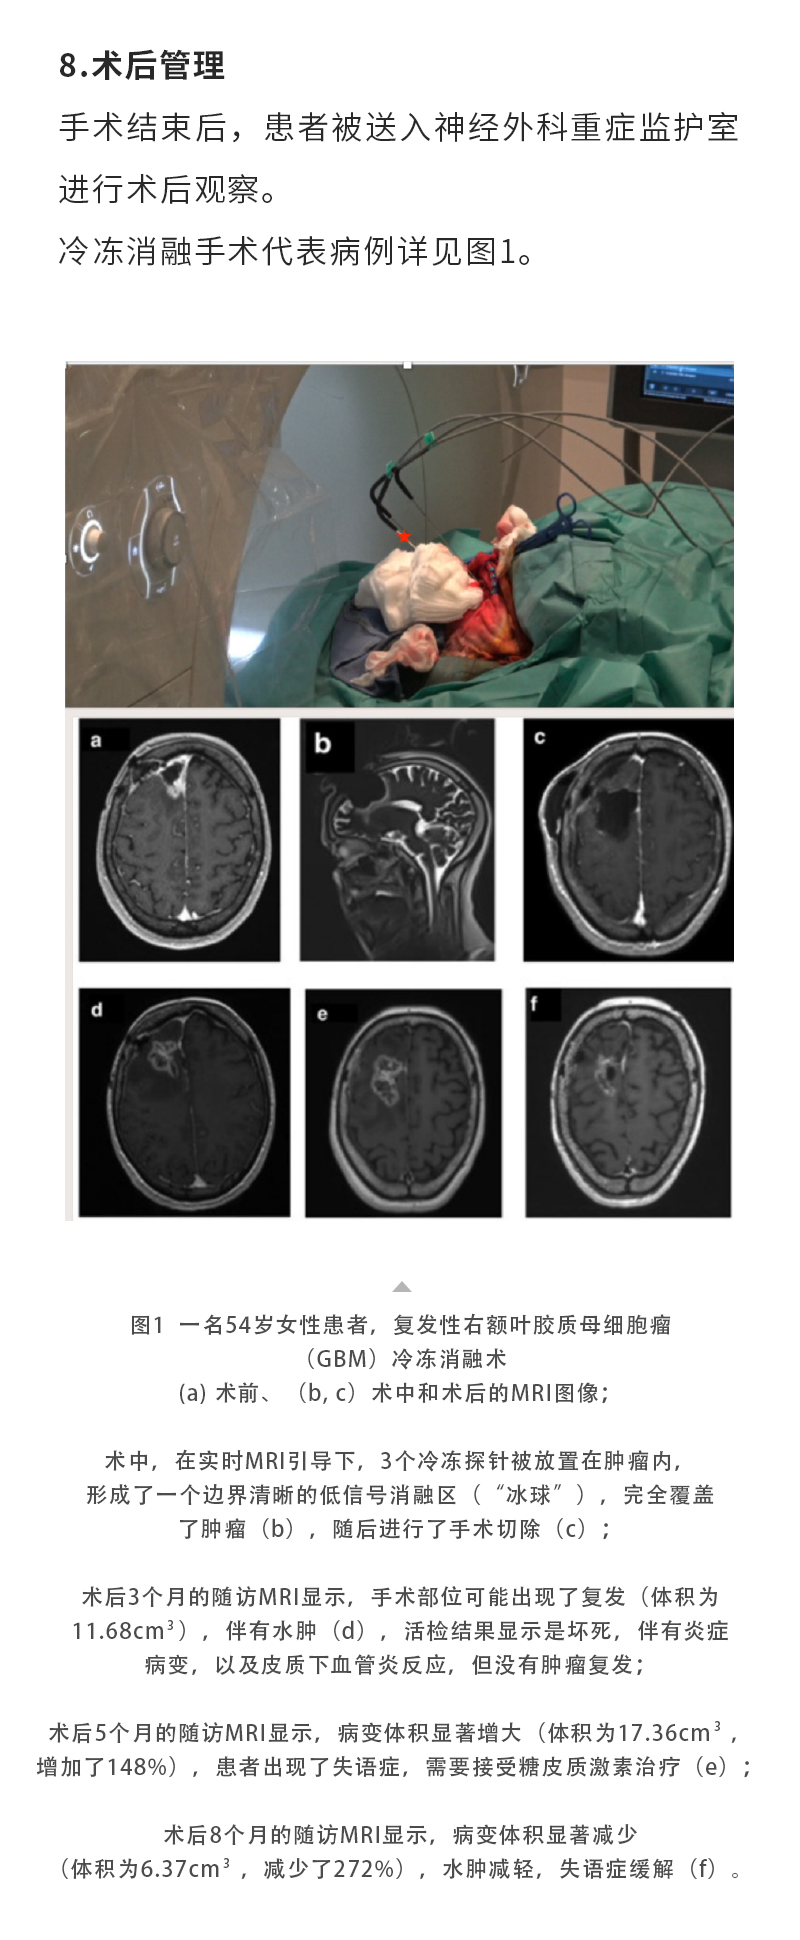

日本特黄特色a大片免费高清观看视频_亚洲午夜综合_一女被两男3p做爰视频_丰满少妇久久_欧美激情在线第一页_久久五月激情_亚洲成人激情在线_滚床单又黄又肉细节描写_日韩av综合在线观看_人妖一级片